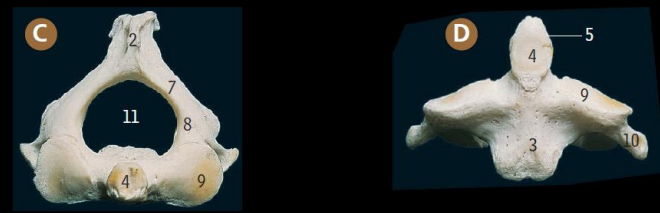

Arch of altlas.

Atlanto-axial joint.

Body of axis.

Lateral mass of axis

Inferior articular process; Superior articular process